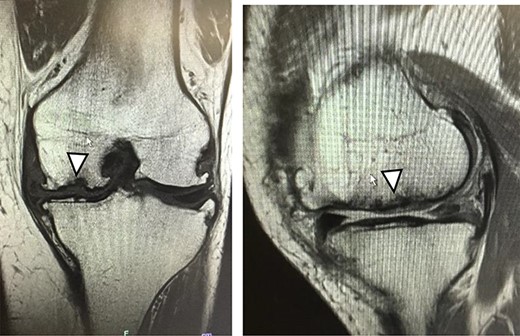

As a control case, a 51-year-old female (BMI, 24.1 kg/m2) presented with 4.5 years of left knee medial joint pain. Preoperative Tegner scores, Lysholm scores and KOOS scores are shown in Table 1. Preoperative radiographs of the left knee joint showed mild medial osteoarthritis (OA) of the knee and hip–knee–ankle (HKA) angle of 1.3-degree varus. MRI showed cartilage injury at the MFC (Fig. 6). Approximately 0.5 g of the healthy cartilage was harvested from less weight-bearing regions of the intercondylar notch using arthroscopy. The specimen was sent to J-TEC for cartilage culture. At 4 weeks after the harvest, the microfracture was performed at a 4-mm power pick at the cartilage lesion, and the two-stage implantation of tissue-engineered cartilage-like tissue (JACC) was performed on the cartilage injury site (4.5 × 5.5 cm; Outerbridge classification, Grade III), and then the tissue implantation site was covered with periosteum taken from the tibia of the same patient (Fig. 7). Knee joints were immobilized for 4 weeks with a soft knee brace. A ROM exercise is started with a continuous passive motion device at 3 weeks after surgery. Partial weight-bearing (30% body weight) was allowed at 4 weeks, and full weight-bearing permission was given from 8 weeks after the surgery.

MRI findings at 1 year after the surgery indicated signal intensity area in the grafted area for the patient with JACC (Fig. 8), whereas the patient who underwent Reveille CP exhibited greater thickness at the grafted area as compared to the surrounding healthy cartilage (Fig. 9). The MOCART score at 1 year after the Reveille CP surgery (60 points) was higher than that of JACC (50 points).

One year after JACC, MRI showed T2 high intensity area in the graft area (arrowhead).